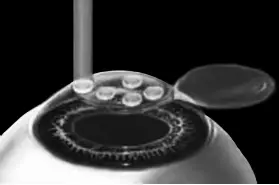

Рис. 6.Луч эксимерного лазера испаряет на роговичном ложе несколько микрон стромы роговицы.

Иллюстрация с сайта Международного лазерного центра www.optics.ru